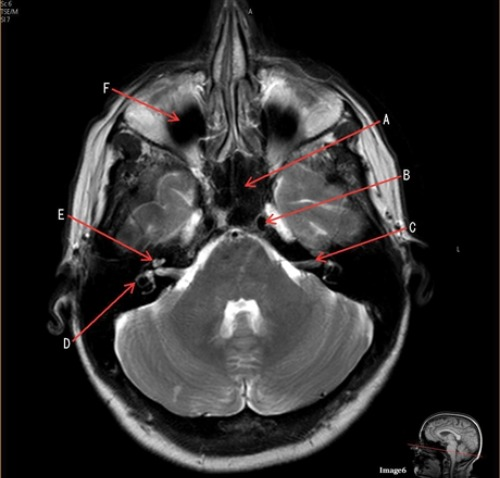

Letter C in Image 6 is pointing to:

A. 7th cranial nerve

B. Cochlea

C. Trigeminal nerve

D. Semicircular canal

Letter B in Image 6 is pointing to:

A. Maxillary sinus

B. Sphenoid sinus

C. Vertebral artery

D. Internal carotid artery

Letter D in Image 6 is pointing to:

Letter E in Image 6 is pointing to:

Letter F in Image 6 is pointing to:

C. Frontal sinus

D. Optic chiasm

Letter A in Image 6 is pointing to:

Image 6 is an example of a ____ weighted sequence acquired in the _____ imaging plane.

A. T1; Axial

B. T1; Coronal

C. T2; Axial

D. T2; Coronal

E. STIR; Axial